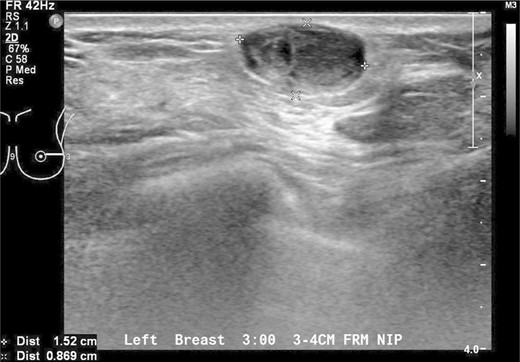

A 37-year-old Chinese female presented with a lump in the left breast that was slowly growing over a duration of 8 years. Aside from a history of amenoblastoma of the jaw which was excised 3 years ago, she has no significant medical history. On physical examination a firm 1-cm nodule was palpable at the 3 o'clock position of the left breast. Mammography showed a well-circumscribed opacity in the left breast (Fig. 1) and ultrasound revealed an ovoid 1.5 × 1.5 × 0.9 cm heterogeneous solid hypoechoic nodule with well-defined, regular margins (Fig. 2). The lesion contained some anechoic areas suggestive of cystic clefts which are consistent with sonographic features of a phyllodes tumour [1, 2].

Sonographic views of an ovoid well-marginated nodule containing some cystic clefts. This lesion was initially thought to represent a phyllodes tumour.

On mammography, most schwannomas appear as well-circumscribed opacities. In certain cases, they may be mammographically occult or may present as ill-defined soft tissue densities [3]. Sonographically, they are generally described as well-defined hypoechoic lesions. Other features suggestive of a schwannoma on ultrasound include target sign (hyperechoic centre and hypoechoic periphery), posterior acoustic enhancement and peripheral nerve continuity. However, these features may also represent other peripheral nerve sheath tumours like neurofibromas [8]. The mass in our patient had cystic areas which were also reported by Lee [5] and Uchida [3].